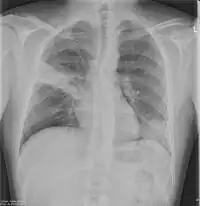

Chest X-rays and X-ray computed tomography (CT) can reveal areas of opacity (seen as white), indicating consolidation.[13] CAP does not always appear on x-rays, sometimes because the disease is in its initial stages or involves a part of the lung not clearly visible on x-ray. In some cases, chest CT can reveal pneumonia not seen on x-rays. However, congestive heart failure or other types of lung damage can mimic CAP on x-ray.[15]

When signs of pneumonia are discovered during evaluation, chest X-rays and examination of the blood and sputum for infectious microorganisms may be done to support a diagnosis of CAP. The diagnostic tools employed will depend on the severity of illness, local practices and concern about complications of the infection. All patients with CAP should have their blood oxygen monitored with pulse oximetry. In some cases, arterial blood gas analysis may be required to determine the amount of oxygen in the blood. A complete blood count (CBC) may reveal extra white blood cells, indicating infection.

Ceftriaxone and azithromycin are often used to treat community acquired pneumonia, which usually present with a few days of cough, fever, and shortness of breath. Chest x-ray typically reveals a lobar infiltrate (rather than diffuse).[19]

X-ray findings indicating hospitalization include:

- Involvement of more than one lobe of the lung

- Presence of a cavity

- Pleural effusion